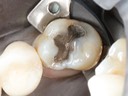

Kyle Chock #18 amalgam removal